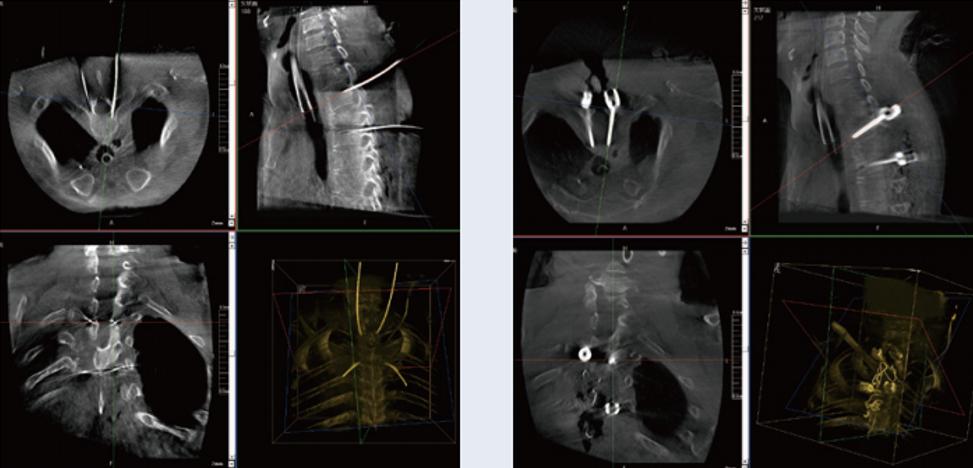

螺釘規(guī)劃后的圖像

植入螺釘后的圖像

術(shù)中三維C形臂與脊柱導(dǎo)航機器人配合應(yīng)用,實現(xiàn)準確定位,確保了手術(shù)安全、高效完成。術(shù)后二維、三維影像顯示手術(shù)效果良好,達到預(yù)期目的。

普愛醫(yī)療三維C形臂提供了高質(zhì)量的術(shù)中實時三維圖像數(shù)據(jù),保障了脊柱導(dǎo)航機器人手術(shù)的準確度和安全性,取得不錯的手術(shù)效果。同時,術(shù)中三維C形臂特有的斷層成像,能幫助醫(yī)生在術(shù)中非常直觀地判斷螺釘植入的準確度。